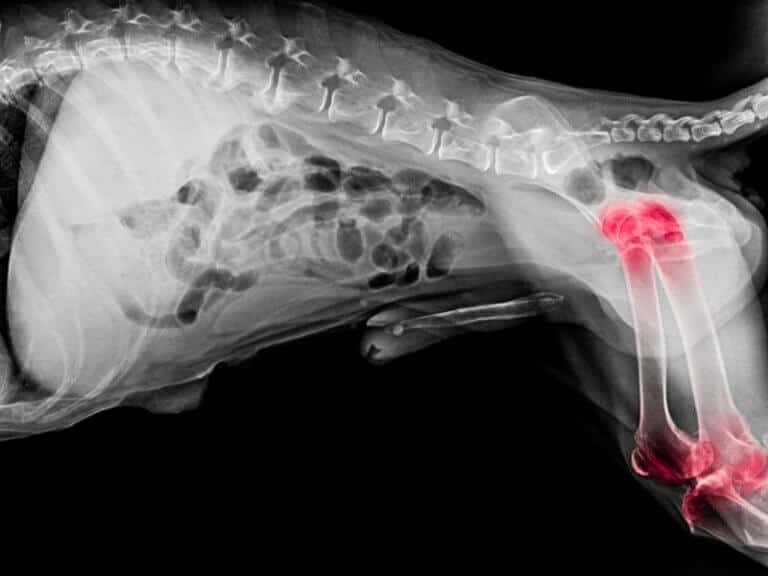

La displasia dell’anca nel cane: cos’è, sintomi, cause e cura

La displasia dell’anca è una malattia che si manifesta nella fase di crescita del cane e consiste in una malformazione delle articolazioni che provoca dolore e rende difficile la normale vita quotidiana del cane che ne è colpito.